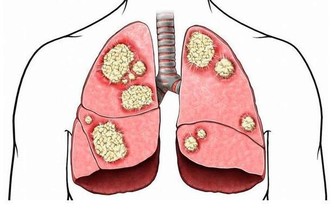

宿便所產生的毒素,會造成很多的問題,引起便祕的原因很多,

也很複雜,幫助排便,促腸蠕動的方法俯拾即是,還是很多人受便祕的困擾,